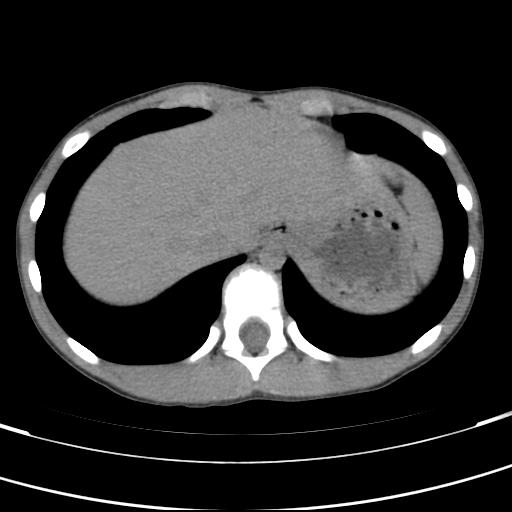

标题: PED3157:左肾缺如,请教脾脏的改变?、、

男孩,9岁。胃部不适。

脾脏位于左侧,但数个脾脏呈分离状态,左肾缺如,右肾代偿肥大。考虑多脾综合征。